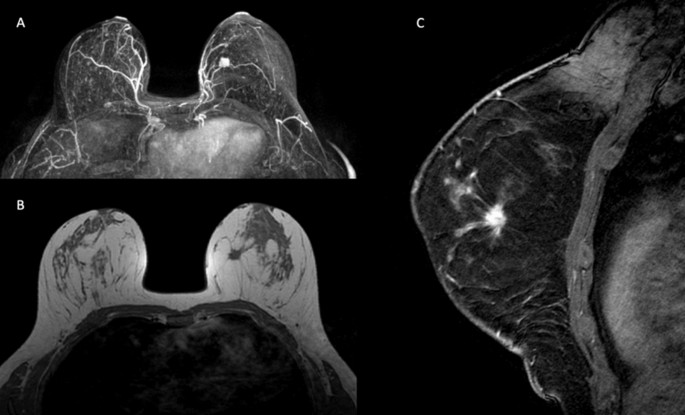

The correlation between MRI features and tumour immunophenotype revealed significant associations with mass shape, margins, internal enhancement and delayed phase of the kinetic curve (Table 2). Oval or round shape and rim enhancement were most frequently observed in triple-negative and luminal ER-low-positive tumours (Fig. 2). Spiculated margins were most frequent in luminal A and luminal B tumours (Fig. 3). A persistent kinetic curve was more frequent in luminal A tumours, while a washout curve was more common in triple-negative, HER2-overexpressing and luminal ER-low-positive immunophenotypes (Fig. 4).

Our results show that luminal ER-low-positive tumours have similar imaging characteristics to triple-negative breast cancer, including similar lesion presentation and mass features (shape, margins, enhancement and late kinetic curve). A round or oval unifocal mass with circumscribed margins, rim enhancement and washout kinetic curve was most frequently observed in luminal ER-low-positive and triple-negative tumours in our sample.

Similar to our findings, many authors have demonstrated that triple-negative breast cancer is usually associated with a round or oval mass with circumscribed margins, rim enhancement and a washout kinetic curve17,20,21,22,23,24. On the other hand, luminal A carcinomas most commonly present as irregularly shaped unifocal masses with spiculated margins14,17. Luminal B carcinomas are mostly associated with heterogeneous internal enhancement15. Multicentric and/or multifocal disease are more commonly found in luminal B and HER2-overexpressing carcinomas25,26. The presence of NME, which is usually related to associated DCIS on pathology, is more frequent in the HER2-overexpressing subtype14,27.